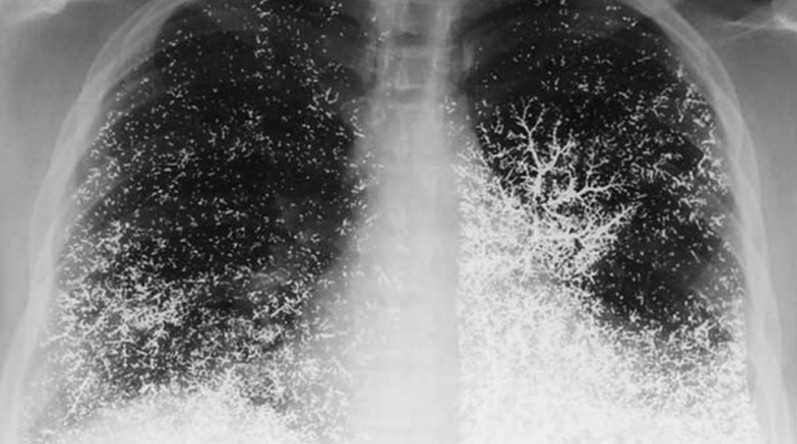

İntihar etmek için damarlarına 10 ml Civa enjekte eden 21 yaşındaki bir diş hekimliği asistanını akciğer görüntüsü. Fotoğrafta civa patikllerinin tüm akciğer damarlarına yayılarak çok ilginç bir görüntü oluşturmak. Neyseki hasta bir hafta sonra toparlanabilmiş

Elemental Mercury Embolism to the Lung

http://www.nejm.org/…[Devamını oku]